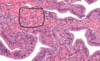

Pineal gland - pinealocytes, interstitial cells, brain sand

Pineal gland: made of nervous tissue, nuclei belong to one of 2 cell types. Larger nuclei that stain lighter belong to pinealocytes (make melatonin). Darker, elongated nuclei are interstitial cells. Brain sand (aggregates of calcified secretions and calcified ECM)

Pineal gland - B&W

Pineal gland: pinealocytes, brain sand ( corpora arenacea )

Pinealocytes of pineal gland